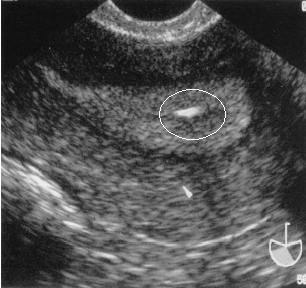

”Le professionalità dedicate”, in questa struttura pubblica, ci dice la dott.ssa Depalo, “preservano il patrimonio gametico dei giovani pazienti, prima del trattamento oncologico, mediante il congelamento delle cellule riproduttive (ovociti e spermatozoi) e le reimpiantano quando la malattia è stata sconfitta. In ragione dell’imperativo della nostra politica sanitaria, che ritiene la riproduzione essere uno degli scopi primari della vita di un essere umano. Ed un figlio - dopo la sconfitta di un tumore - rappresenta la più grande speranza di vita per ognuno di questipazienti. Ci sono già diversi bambini nati da questa pratica e questo risultato ci inorgoglisce”.

“Attualmente nella nostra biobanca sono congelati oltre 6mila dosi di liquido seminale raccolto da giovani uomini (età media 30/22aa) affetti - nel 67.3% dei casi - da neoplasia ed in procinto di iniziare un trattamento radio-chemioterapico. Il 61% di questi pazienti risulta affetto da tumori testicolari”, aggiunge la dottoressa Depalo. “Nel 32.7% dei casi il congelamento del liquido seminale è stato eseguito anche per altre cause,  come ad esempio una severa riduzione del numero e della motilità degli spermatozoi, osservata in particolare nei giovani pazienti provenienti da aree urbane ad alto tasso di inquinamento industriale”.

E a proposito dell’incidenza di richieste di tale trattamento, la dottoressa Depalo precisa: “Circa 200 giovani donne hanno richiesto  l’auto-conservazione dei gameti. Tant’è che nella biobanca che dirigo  abbiamo congelato complessivamente479 ovociti  e 153 frammenti di ovaio. Soltanto il  7% di queste pazienti è risultato affetto da patologie neoplastiche (tumori del sangue, della mammella e dell’apparato genitale), poiché la barriera che limita l’accesso alle donne che intendono preservare la fertilità è il tempo tra le procedure per il recupero di ovociti/ovaio e l’inizio del trattamento antineoplastico. Nel restante le indicazioni hanno evidenziato tumori ginecologici benigni, endometriosi e la menopausa precoce, anche quest’ultima una condizione sempre più frequente nelle giovani donne esposte a inquinanti ambientali”.  Antonio V. Gelormini